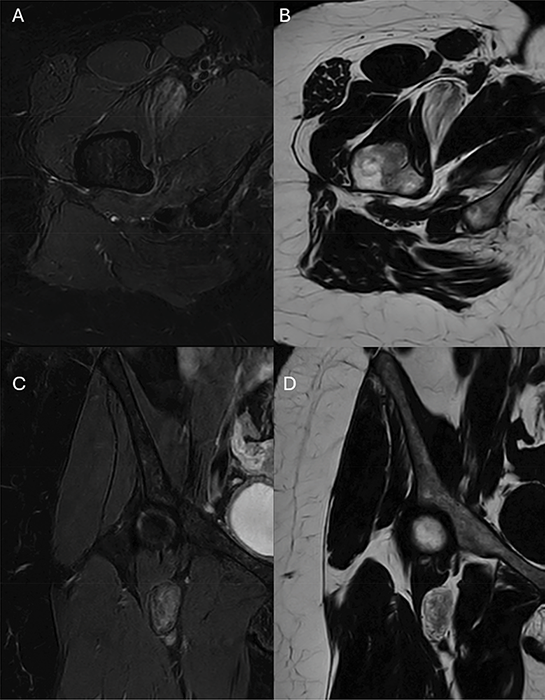

Figure 2

T2 Dixon MRI images demostrate the regions of high signal on the fat‑only images (B and D) corresponding to low signal on the water‑only images (A and C) with interspersed brush‑stroke‑like areas of high signal intensity on the water‑only images and low signal on the fat‑only images.